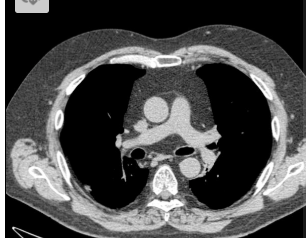

2 anos, masculino

Cisto de duplicação esofágico

TC: Cisto com densidade de líquido, margens bem definidas que podem realçar com contraste; podem complicar com hemorragia, infecção: nível liquido, espessamento parietal.